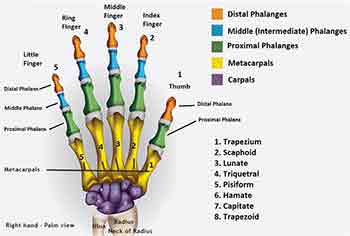

Problems involving the wrist and hand are increasingly common. They are often due to a fall or fracture and also due to repetitive strain syndromes. Sometimes they involve an arthritic pathology. Mostly they are amenable to mobilization of the joints and stretching of the tendons and muscles of the wrist and hand. I have special expertise in this area having treated many classical musicians for example.

I had a case a month ago of a young guitarist who could no longer use his left little finger properly. I attended to the muscles and tendons which control that finger and improvement followed immediately. With computer workers I will examine their workstation set up and habits especially of mouse usage. This approach combined with my specialized techniques all to often bring about a rapid improvement.

We can all experience nerve related symptoms. Ranging from pins and needles, numbness and partial paralysis of muscles and limbs. Most of these common symptoms can be relieved by the correct diagnosis and treatment. The more serious central nervous system conditions are more problematic but can still be greatly helped especially with their secondary symptoms such as weakness, loss of co-ordination and worse. The most common nerve related symptom is pins and needles in the hand. This may be due to a number factors and is often mis-diagnosed as carpal tunnel syndrome.